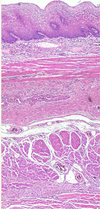

this is a sample from colon. Lable the two layer of muscle that can be seen

215